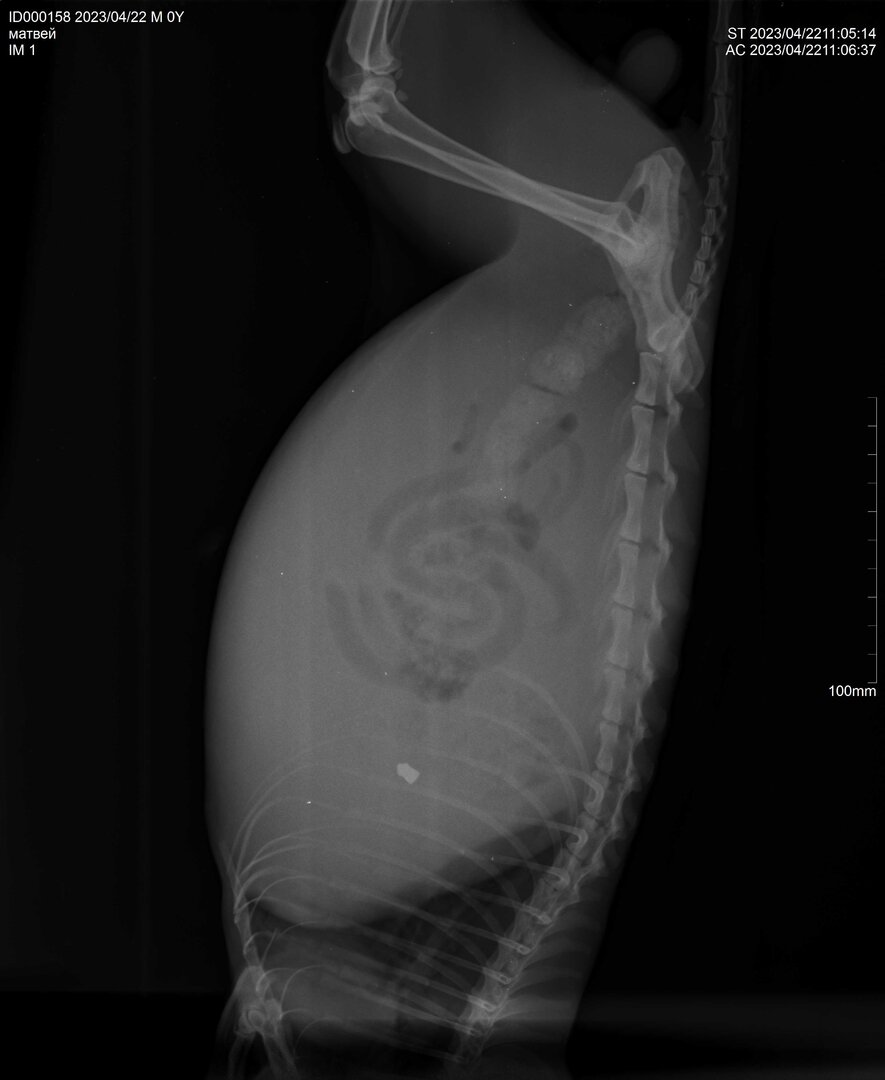

В середине марта, кот Матвей потребовал открыть окно и свалил. Обычное дело для некострированого кота. 16 апреля в Пасху появился на заборе, жалобно мяуча. Зашел так же через окно, разглядели мы его только дома. Худющий как скелет, а пузо раздуто, как будто он кошка. Двигался пошатываясь, лапы заплетались. Правда на фото особо не видно.

Только в минувшую субботу смогли свозить к ветеринару. Сделали рентген . Вот результат, плядь!

Раздутый живот - жидкость в брюшной полости.

Пулька от пневмовинтовки, если правильно понял. Только не полая, а утяжеленная, сказали в печени сидит, но не похоже, где-то в районе легкого. И пружина, скорее всего, у винтовки усиленная была, далеко не 7,5 Дж.